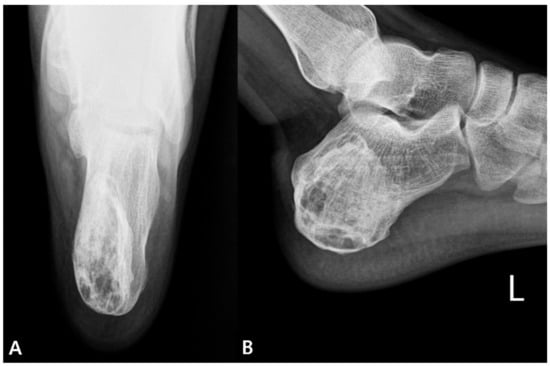

2. Case Presentation

2.1. Preoperative Evaluation